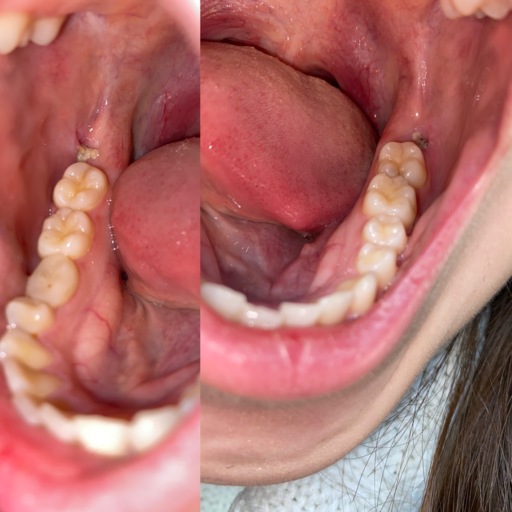

Is my widom Tooth Socket healing normally?

It's day 2 post surgery and I'm noticing grey inside my socket. Is it healing normally? Pain is not too bad although I'm taking ibuprofen every six hours. I'm using salt water rinses after ever meal. I want to be sure I don't have dry socket. I'm eating soft foods, not using the syringe yet. How long does it take to heal completely?

After a tooth is extracted it can take up to six weeks before the site is completely healed. Initial closure takes places in approximately 2 weeks. Continue to keep the area clean and begin warm salt water rinses at least twice daily. This will help the tissues remaing clean and free of debris. Be sure not to eat a lot of seeds, nuts or granola during healing. These types of foods can be hard to dislodge from the socket. If you start having pain, similar to what a toothache feels like, it may be a dry socket. Your dentist can place a medicated paste which will provide almost immediate relief. Do not be afraid to have your dentist evaluate the extraction site if you feel something is not correct It is better to treat a dry socket sooner than later.